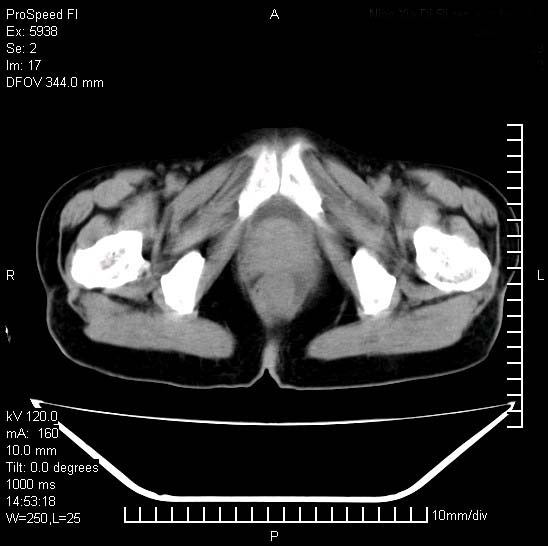

反复小腹疼痛,盆腔积液3年,无发热,曾抗痨一段时间。

右下腹肠管壁增厚,边缘有侵润改变及点状低密度影,内侧可见局限性肿块。考虑-----淋巴瘤或增生型肠结核----盆腔积液-----建议肠镜检查

考虑盆腔及右下腹感染性病变(结核可能)。

结核性腹膜炎伴积液。右侧髂骨骨窗看看,是否有骨质破坏。

提示结核性腹膜炎合并盆腔积液。建议查ppd或tb抗体。